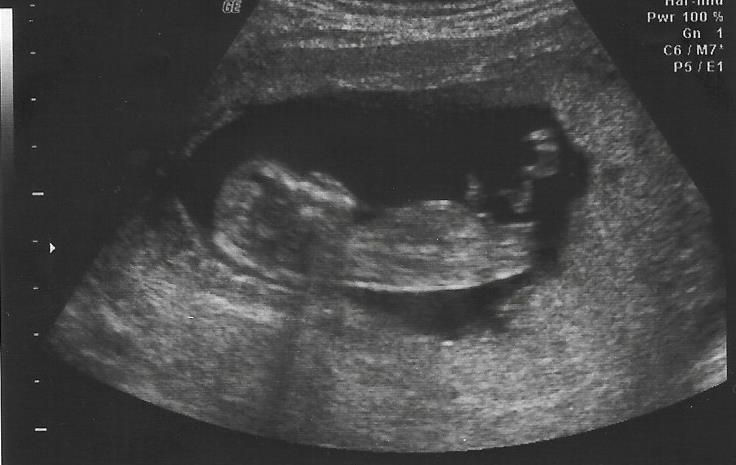

This is from 11w6d. I know its a little early. I immediately thought girl when I saw it and honestly we were kind of hoping for a boy but I thought I would get a second opinion. Thanks!

The top pic does look girlie but as your only 11 weeks theres still time for it to rise x

Hmm...it IS too early, but based on these pictures I think girl.

It is early, but I will go with Pink lean

During the ultrasound I saw a forked end too that was also just as flat. I was trying so hard to see something that would make me possibly think boy but never did. The tech was going to peek but the cord was between the legs (though I now it's too early for a potty shot). I will be in love either way!

Girly nub, but it's a little early I think. :) It could rise! :)